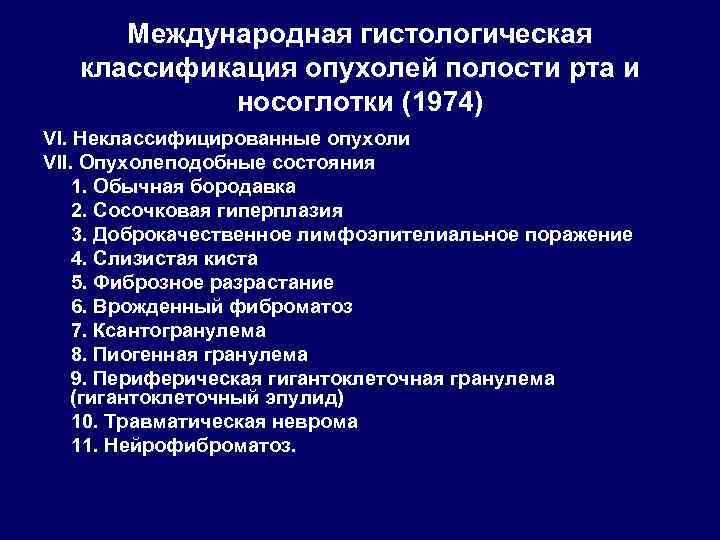

Международная гистологическая классификация опухолей полости рта и носоглотки (1974) VI. Неклассифицированные опухоли VII. Опухолеподобные состояния 1. Обычная бородавка 2. Сосочковая гиперплазия 3. Доброкачественное лимфоэпителиальное поражение 4. Слизистая киста 5. Фиброзное разрастание 6. Врожденный фиброматоз 7. Ксантогранулема 8. Пиогенная гранулема 9. Периферическая гигантоклеточная гранулема (гигантоклеточный эпулид) 10. Травматическая неврома 11. Нейрофиброматоз.

Международная гистологическая классификация опухолей полости рта и носоглотки (1974) VI. Неклассифицированные опухоли VII. Опухолеподобные состояния 1. Обычная бородавка 2. Сосочковая гиперплазия 3. Доброкачественное лимфоэпителиальное поражение 4. Слизистая киста 5. Фиброзное разрастание 6. Врожденный фиброматоз 7. Ксантогранулема 8. Пиогенная гранулема 9. Периферическая гигантоклеточная гранулема (гигантоклеточный эпулид) 10. Травматическая неврома 11. Нейрофиброматоз.